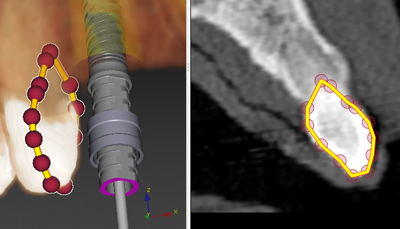

A line annotation is used to create a line segment or contour to delineate or mark anatomical structures.

Use this tool for example to delineate a tooth.

Click another position on the object. A second gray sphere appears and a connecting yellow line is drawn. This default line color can be changed using the right-click pop-up menu of the line annotation.

When indicating a contour line and hovering over an already defined point (generated during this action), it is possible to ‘re-use’ the point by clicking it. As such, a closed contour (as shown in the image above) or a 'figure eight' can be drawn.